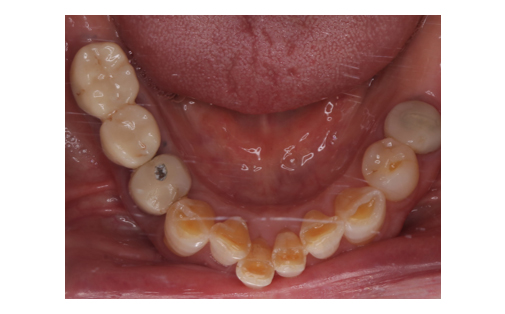

骨造成とインプラント

Before

下顎の骨量が乏しいため骨造成をし、その後インプラント治療を行いました。

かみ合わせも良好でしっかりと機能しています。